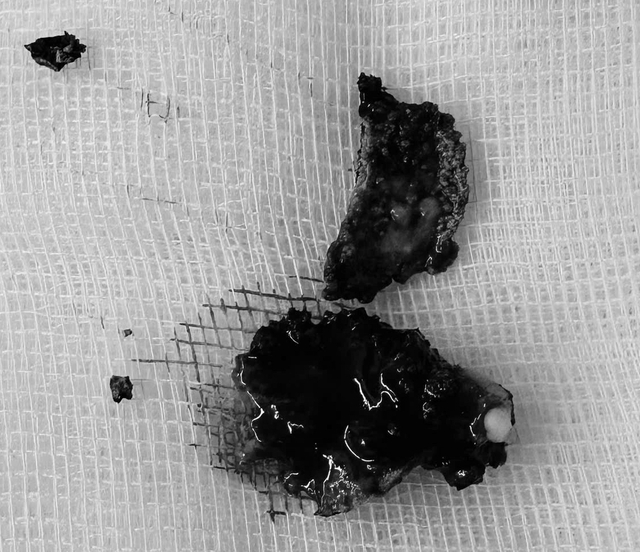

Dị vật được các bác sĩ lấy ra khỏi mũi bệnh nhân.

Để điều trị dứt điểm cho bệnh nhân, các bác sĩ tiến hành phẫu thuật nội soi, lấy dị vật có kích thước khoảng 2 cm ra ngoài. Sau đó, bệnh nhân được chỉnh hình vách ngăn mũi, giúp đường thở thông thoáng hơn.